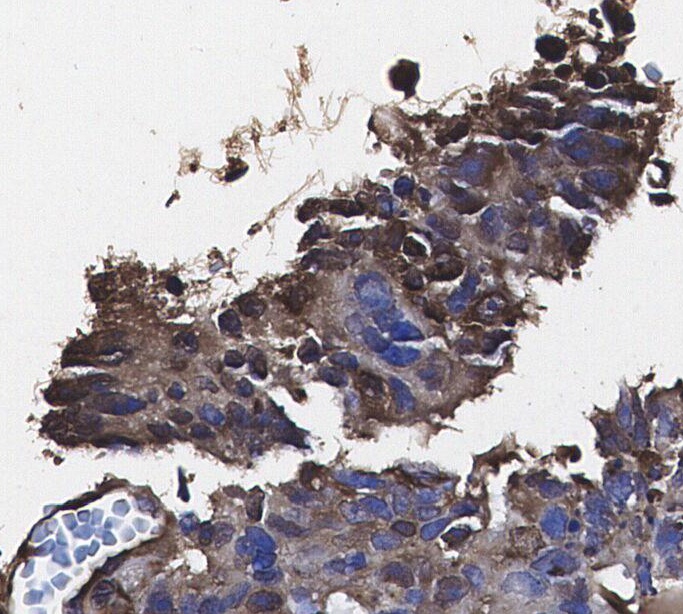

• Immunohistochemical analysis of formalin fixed paraffin embedded human Colorectal cancer tissue with F0235 at 1/100 dilution.